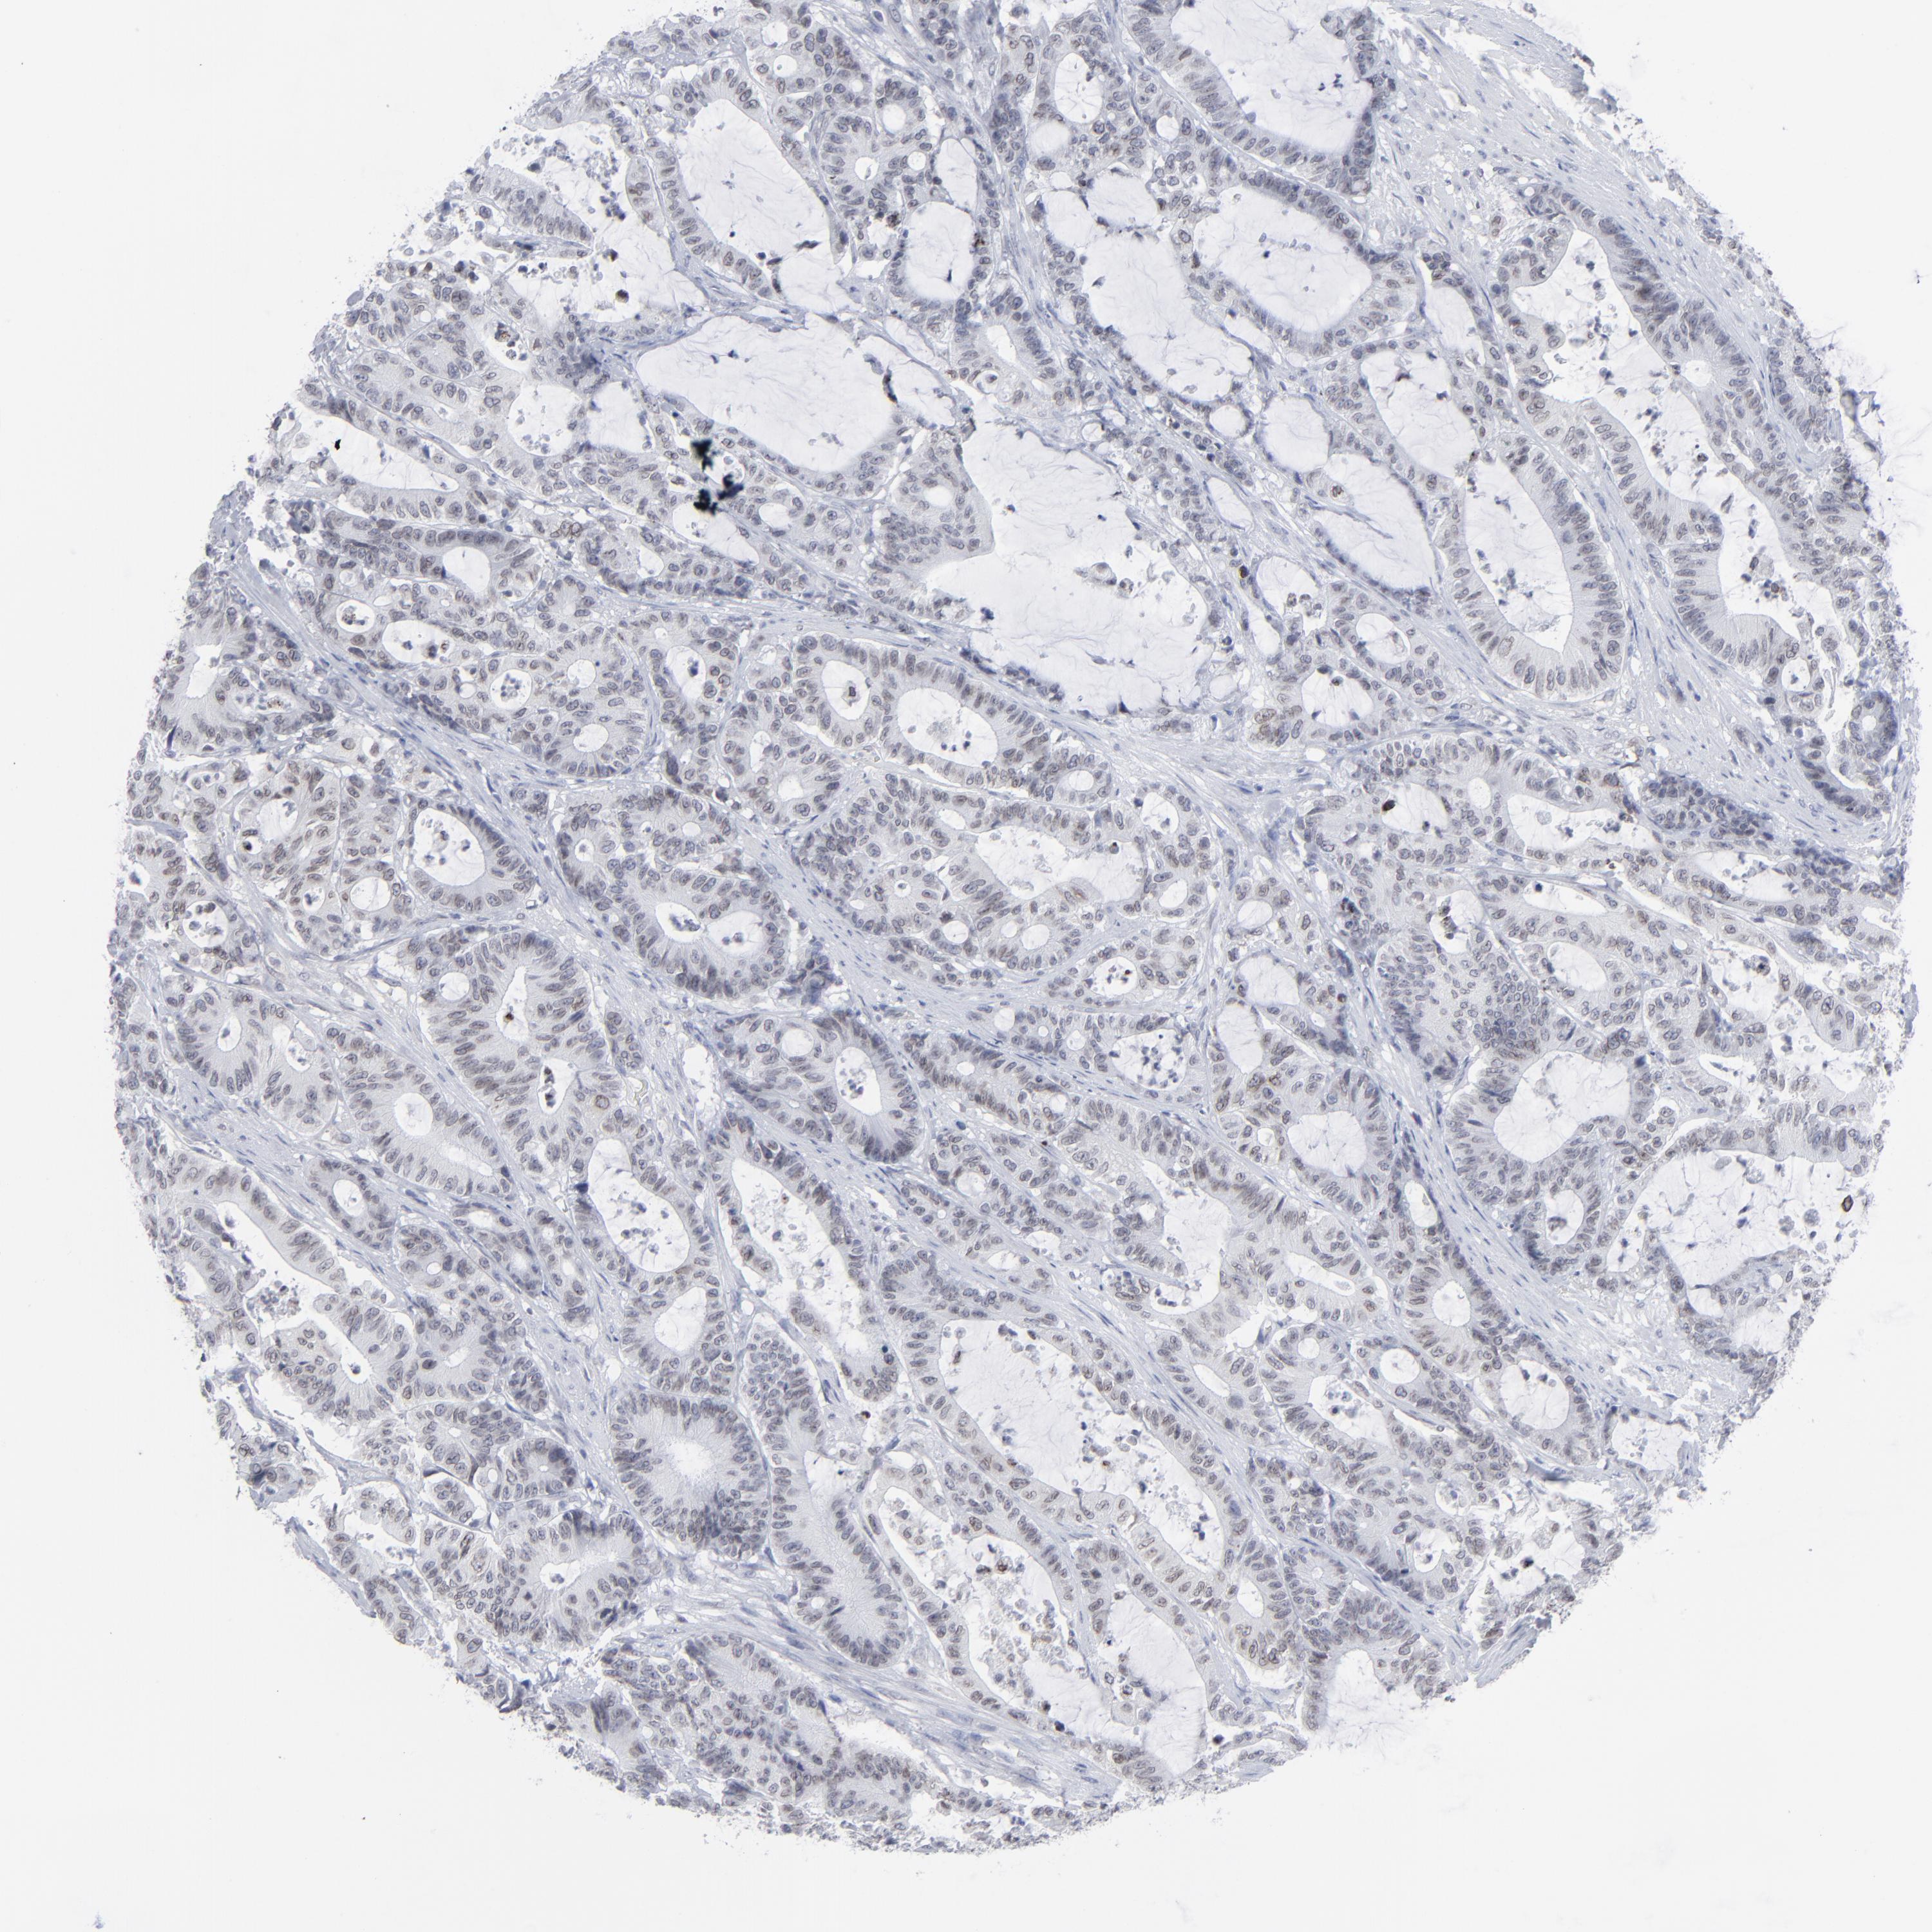

ANTIBODIES

AND

VALIDATION